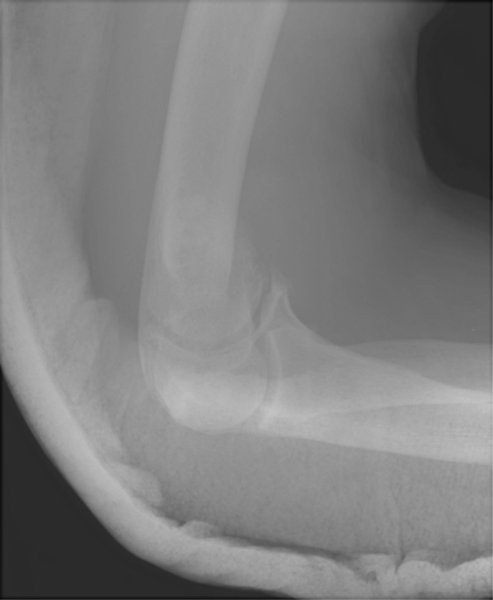

Return to Supracondylar Fracture (Humerus)